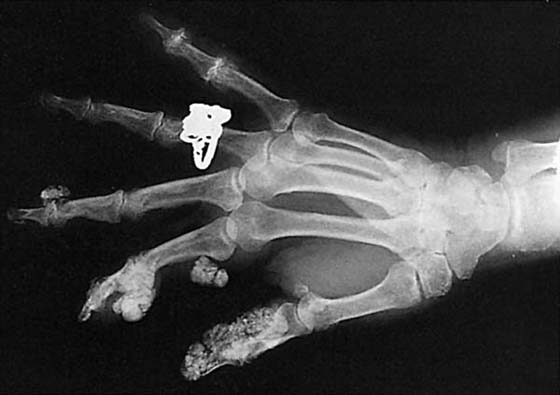

Bone density, which is evaluated grossly, may be normal, less than normal (osteopenia), or greater than normal (osteosclerosis). Osteopenia is most often encountered in the elderly and is known as senile osteoporosis when associated with advanced age. Osteosclerosis occurs in conditions such as avascular necrosis (AVN) (Fig. 13-2), fracture healing, and metabolic bone disease.2 Plain films may reveal discrete or diffuse bone lesions, including primary or metastatic bone tumors, infection, and metabolic bone disease (Fig. 13-3). The cortical integrity is carefully inspected for evidence of acute fracture (Fig. 13-4) and the joint alignment evaluated for subluxation or dislocation.3 Abnormalities of the articular surface and cartilage joint space also are documented. Narrowing of the cartilage space may indicate arthritis, resulting from degeneration, inflammation, infection, or trauma (Figs. 13-5 and 13-6).4 Finally, the soft tissue shadows are evaluated for irregularities. Any evidence of calcification (Fig. 13-7), foreign bodies (Fig. 13-8, online),5 or soft tissue masses must be correlated with the clinical findings.

Figure 13-3 An enchondroma is demonstrated in this posteroanterior view. Note the decreased bone density of the fourth metacarpal head and shaft, which also are increased in size. Within the area of decreased bone density are stippled calcifications—a classic finding in this type of lesion.